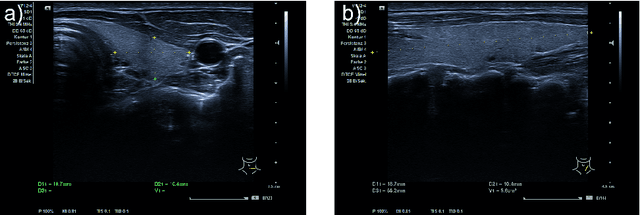

Abstract:Background: Thyroid volumetry is crucial in diagnosis, treatment and monitoring of thyroid diseases. However, conventional thyroid volumetry with 2D ultrasound is highly operator-dependent. This study compares 2D ultrasound and tracked 3D ultrasound with an automatic thyroid segmentation based on a deep neural network regarding inter- and intraobserver variability, time and accuracy. Volume reference was MRI. Methods: 28 healthy volunteers were scanned with 2D and 3D ultrasound as well as by MRI. Three physicians (MD 1, 2, 3) with different levels of experience (6, 4 and 1 a) performed three 2D ultrasound and three tracked 3D ultrasound scans on each volunteer. In the 2D scans the thyroid lobe volumes were calculated with the ellipsoid formula. A convolutional deep neural network (CNN) segmented the 3D thyroid lobes automatically. On MRI (T1 VIBE sequence) the thyroid was manually segmented by an experienced medical doctor. Results: The CNN was trained to obtain a dice score of 0.94. The interobserver variability comparing two MDs showed mean differences for 2D and 3D respectively of 0.58 ml to 0.52 ml (MD1 vs. 2), -1.33 ml to -0.17 ml (MD1 vs. 3) and -1.89 ml to -0.70 ml (MD2 vs. 3). Paired samples t-tests showed significant differences in two comparisons for 2D and none for 3D. Intraobsever variability was similar for 2D and 3D ultrasound. Comparison of ultrasound volumes and MRI volumes by paired samples t-tests showed a significant difference for the 2D volumetry of all MDs, and no significant difference for 3D ultrasound. Acquisition time was significantly shorter for 3D ultrasound. Conclusion: Tracked 3D ultrasound combined with a CNN segmentation significantly reduces interobserver variability in thyroid volumetry and increases the accuracy of the measurements with shorter acquisition times.